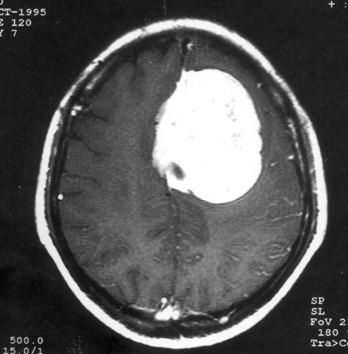

问题 病历摘要:??患者,男,40岁。发作性左下肢抽搐1年余,每次发作3~5分,每周发作1~2次。每次发作后感左下肢乏力,约半日后可自行恢复。既往身体健康。体检:神清,头顶部偏右有局限性骨性隆起(1.5×1.5cm),左鼻唇沟稍浅,伸舌居中。感觉、运动无明显异常。左浅反射减退,左下肢腱反射稍亢进,左Babinski征(-)。 下列对该患者的临床特点分析哪些是正确的?

选项 A.有Jackson癫痫发作 B.有Todd氏麻痹 C.有精神运动性癫痫发作 D.右中央前回可能有刺激性病灶存在 E.右中央后回可能有破坏性病灶存在 F.有失张力发作 G.右锥体束征(+) H.有颅内高压表现

答案 ABDG

解析 ABDG